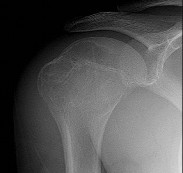

A 24-year-old rugby player has recurrent anterior shoulder instability with 25% anterior glenoid bone loss on a 3D CT scan.

A Latarjet procedure is performed. What is the primary biomechanical stabilizing mechanism of this procedure when the shoulder is in the apprehension position (abduction/external rotation)?

Explanation

The Latarjet procedure involves transferring the coracoid process with the attached conjoined tendon to the anterior glenoid. While the bony block restores the glenoid arc (the 'bony effect'), biomechanical studies have demonstrated that the primary stabilizing mechanism in abduction and external rotation is the dynamic 'sling effect.' The conjoined tendon acts as a hammock against the inferior capsule and lower subscapularis, preventing anterior translation of the humeral head.